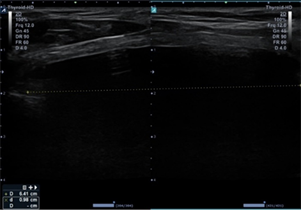

Baseline evaluation and ultrasound were

performed in the office (Figure 1).

a) Photo

b) Ultrasound image - AP and transverse view

c) Ultrasound image – lateral view

Figure 1: Baseline images before

intervention